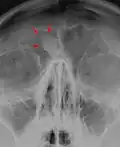

Остеома лобной пазухи на рентгене -